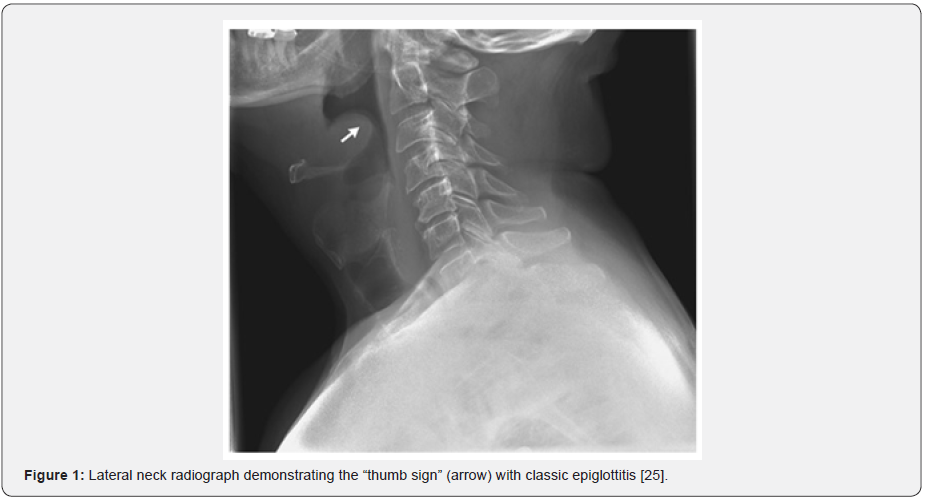

Diagnosis

The diagnosis of epiglottitis is primarily a clinical diagnosis. Avoiding instrumenting the oropharynx during examination will reduce progression of epiglottic oedema leading to potential airway disaster. A lateral neck radiograph may show swelling of the epiglottis due to epiglottic fold oedema called “thumb sign” (Figure 1) [18]. The radiograph is not necessary, although can be used to eliminate differential diagnoses (epiglottic abscess, parapharyngeal abscess, or retropharyngeal abscess). Imaging is performed in hemodynamically stable and cooperative patients. Adults may have obliteration of the vallecula known as the “vallecula sign” from an oedematous epiglottis [19]. Flexible laryngoscopy is best completed in a safe and controlled setting such as the operating theatre as there may be a risk of laryngospasm and imminent airway obstruction. Once a clinical diagnosis of epiglottitis is made, the patient needs to be transferred to the operating room for airway examination. In an adult, indirect, direct, and flexible laryngoscopies are accurate, safe and have not been demonstrated to exacerbate airway obstruction [18].